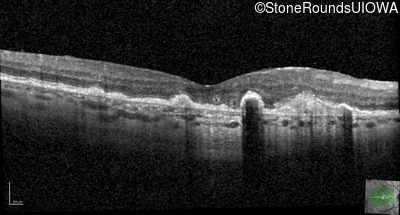

Malattia Leventinese (IIJ)

Malattia Leventinese (IIJ)

This 43 year old woman has experienced a gradual reduction in her central vision for the past 3 years.

| Malattia Leventinese | EFEMP1 | Arg345Trp CGG>TGG | AD |